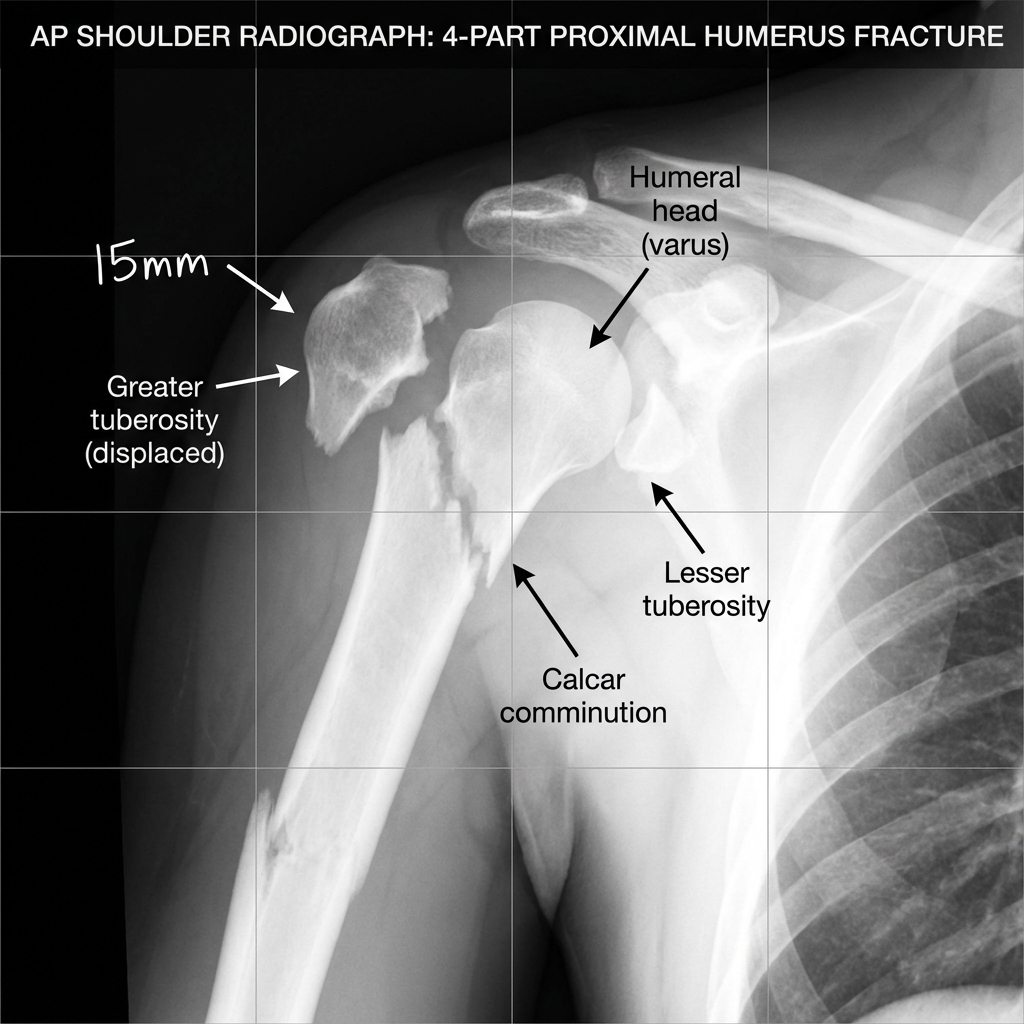

Clinical image for Proximal Humerus Fracture

Source: Educational radiograph of a 4-part proximal humerus fracture • OrthoVellum Medical Education Team • OrthoVellum Educational Use